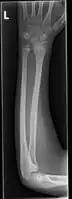

| Midshaft fracture of the radius and ulna | |